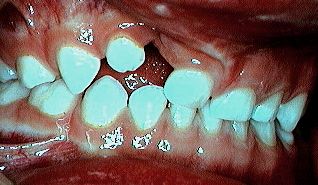

On est en période de denture mixte; le patient est âgé de 9 ans. C'est le moment idéal pour planifier la greffe osseuse: celle-ci doit se faire impérativement avant l'éruption de la canine permanente. Grâce à l'apport d'os de greffe, la canine pourra faire son éruption dans un environnement osseux normalisé. Au cours de son éruption, cette dent contribuera activement à l'intégration de la greffe en stimulant son organisation et son remodelage (voir Fig.7 à 12).

Grâce à la greffe, la canine permanente sera en mesure de faire son éruption spontanée sur l'arcade et elle bénéficiera d'un environnement osseux normalisé, son alignement orthodontique sera possible et, plus important encore, les perpectives de stabilité à long terme de cette dent et de ses voisines seront sensiblement améliorées.

2) La canine permanente peut faire son éruption dans un os normalisé. (Fig.12). Elle pourra être redressée, alignée (Fig.13) et rapprochée des dents voisines en conservant un support osseux normal (Fig.10 & 11).